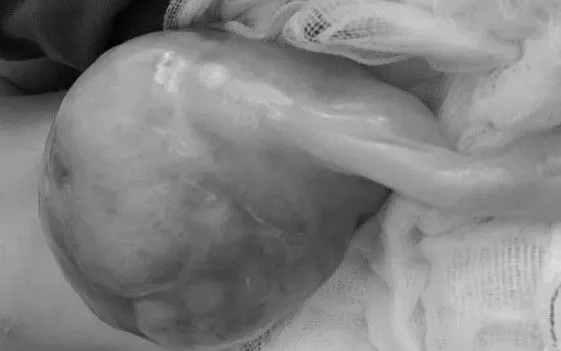

Hồi cuối tháng 9, bệnh nhi L.H.D., chào đời với khối thoát vị rốn kích thước lên tới 15x14x13 cm, trong đó gan và ruột sa hoàn toàn ra ngoài thành bụng. Dị tật được phát hiện từ tuần thai thứ 13 qua siêu âm, nên ngay sau sinh, bệnh nhi được đặt nội khí quản và chuyển thẳng đến Khoa Hồi sức tích cực Ngoại để xử trí.

Bệnh nhi sơ sinh chào đời với khối thoát vị rốn “khổng lồ”. Ảnh BV

Với những trường hợp nhẹ, khối thoát vị có thể tự xẹp. Tuy nhiên, nếu nội tạng chui qua lỗ thoát vị khiến bụng chướng, có nguy cơ tắc nghẽn, hoại tử ruột, cần can thiệp cấp cứu. Trường hợp của bệnh nhi này là khối thoát vị lớn nhất từ trước đến nay mà khoa tiếp nhận xử trí.

Theo BSCKII. Tạ Thị Quỳnh Anh, phẫu thuật là phương pháp điều trị duy nhất đối với thoát vị rốn. Thời điểm lý tưởng là trong 6 giờ đầu sau sinh, nhưng chỉ áp dụng nếu khối thoát vị không quá lớn (đường kính vòng rốn dưới 6 cm) và đóng bụng không làm tăng áp lực ổ bụng. Với trường hợp của bé L.H.D., do khối thoát vị quá khổng lồ và thể trạng trẻ còn non yếu, việc can thiệp phải trì hoãn để chờ quá trình biểu bì hóa hoàn chỉnh trước khi đưa dần các tạng trở lại ổ bụng.